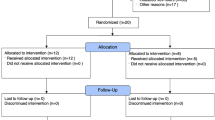

The study was approved by the Regional Ethics Committee of Copenhagen (approvals H20023159 and H22009131) and registered at ClinicalTrials.gov (NCT04354584). A total of 11 CARDS patients were included in the present study. Data on compartmental immunophenotyping on four patients recruited during the first wave have previously been reported elsewhere2. Furthermore, four non-COVID-19 patients with moderate-to-severe ARDS and 15 healthy controls from a previous study were included for comparison8. Since all patients were incompetent, informed consent was obtained from next of kin, and the BAL procedure was performed within less than 72 h of mechanical ventilation.